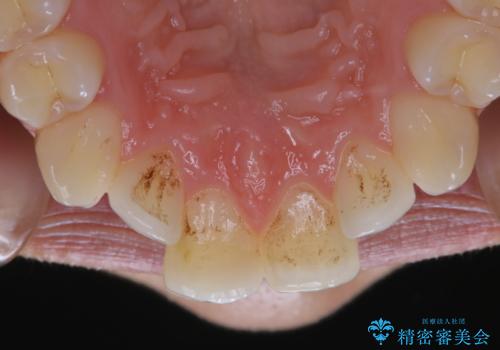

プラークが放置されると、そこで病原菌が繁殖し始めます。そうなるとバイオフィルム(歯面に強固に付着したばい菌の膜)になり、歯肉に炎症が生じ歯周病の引き金となります。

プラークやバイオフィルムといった細菌などを放置すると歯石となります。歯石になってしまうと歯磨きでは取り除くことができないため、歯科医院にて専門的な機械や材料を使用してクリーニングを受ける必要があります。

PMTCは審美的な面だけではなく、虫歯や歯周病予防にもなります。虫歯や歯周病予防のためには、お口の中を清潔に保つことが大切です。